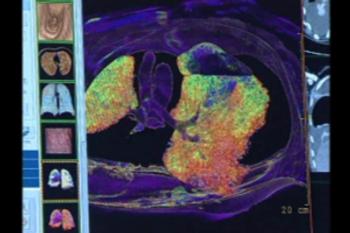

The most common chest injury identified in the study was pulmonary contusion, or bruising of the lung, occurring in 61 percent of patients. In pulmonary contusion, blood and other fluids collect in the lung tissue, potentially leading to oxygen deficiency.

Other chest injuries included pneumothorax, or collapsed lung (45 percent of patients), and rib fractures (34 percent of patients).

Forty percent of patients with chest injuries required care in the intensive care unit (ICU), compared to 22 percent of patients without chest injuries. Patients with chest injuries also had longer hospital stays. Eight children with chest injuries died.